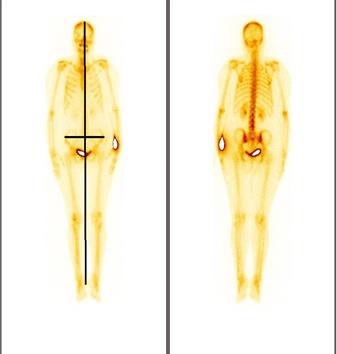

It is easy to use, widely available and less expensive. Moreover it does not use any ionizing radiation, gives a clearer picture of soft tissue that cannot be seen in X-rays, causes no health problems and can be repeated as much as can if indicated for any health problems. It provides real-time-imaging so Is perfectly good for minimally invasive procedures such as needle biopsy and fluid aspiration. The disadvantages if the transrectal USG is that the patients with their bowel removed during or prior surgery are not good candidates for USG of the prostate as it always require a placing a probe into the rectum.

When prostate cancer is suspected, the diagnostic test of choice is a systematic needle biopsy with US guidance. Before biopsy, the patient is prepped with an enema and antibiotics (quinolone analogs). With the patient in the decubitus position, the transrectal US probe is placed in the rectum, the prostate and seminal vesicles are visualized, and the images are recorded in transverse and sagittal planes. And moreover the biopsy can be taken simultaneously under the USG guidance. A single biopsy session has a sensitivity of 70%–80% for the detection of cancer. To minimize the need for repeat biopsy sessions, many physicians obtain more cores the first time. Separate samples of the anterior prostate (or transition zone) are usually not obtained unless previous biopsy sessions have failed to find a suspected cancer (eg, in a patient with a high PSA level, abnormal findings at digital rectal examination [DRE], and multiple negative peripheral zone biopsy specimens), or imaging with transrectal US or MR suggests an anterior cancer [[103]].

Diagnostically, transrectal US is used to measure the volume of the prostate gland, an important factor in computing “PSA density” (serum PSA level in nanograms per millilitre divided by the volume of the prostate in cubic centimetres). Moreover, the volume as measured with transrectal US can be used in staging and in predictive nomograms. Cancer, depending on its size, grade, and location, usually appears hypoechoic relative to the normal peripheral zone of the prostate (only approximately 1% are hyperechoic). As a diagnostic test for cancer, transrectal US without biopsy is as accurate as DRE and complements the physical examination. Some palpable cancers are not visible at US, and some visible cancers are not palpable. With the shift toward smaller, early-stage cancers, many cancers detected at biopsy are not visible at US (low sensitivity) and many hypoechoic areas do not prove to be malignant at biopsy (low specificity); therefore, transrectal US alone, without the addition of biopsy, has limited value in the detection of cancer [[104]].

Transrectal ultrasound has been used for the staging of primary cancer but is generally considered insufficient. The criterion for identifying extracapsular extension on transrectal US scans are bulging or irregularity of the capsule adjacent to a hypoechoic lesion. The length of the contact of a visible lesion with the capsule is associated with the probability of extracapsular extension. Seminal vesicle invasion (SVI) is heralded by a visible extension of a hypoechoic lesion at the base of the prostate into a seminal vesicle or by echogenic cancer within the normally fluid-filled seminal vesicle. Asymmetry of the seminal vesicles or solid hypoechoic masses within the seminal vesicles are indirect indicators of disease extension. When extraprostatic extension into the seminal vesicles is suspected, additional transrectal US-guided biopsies of the seminal vesicles can be performed.